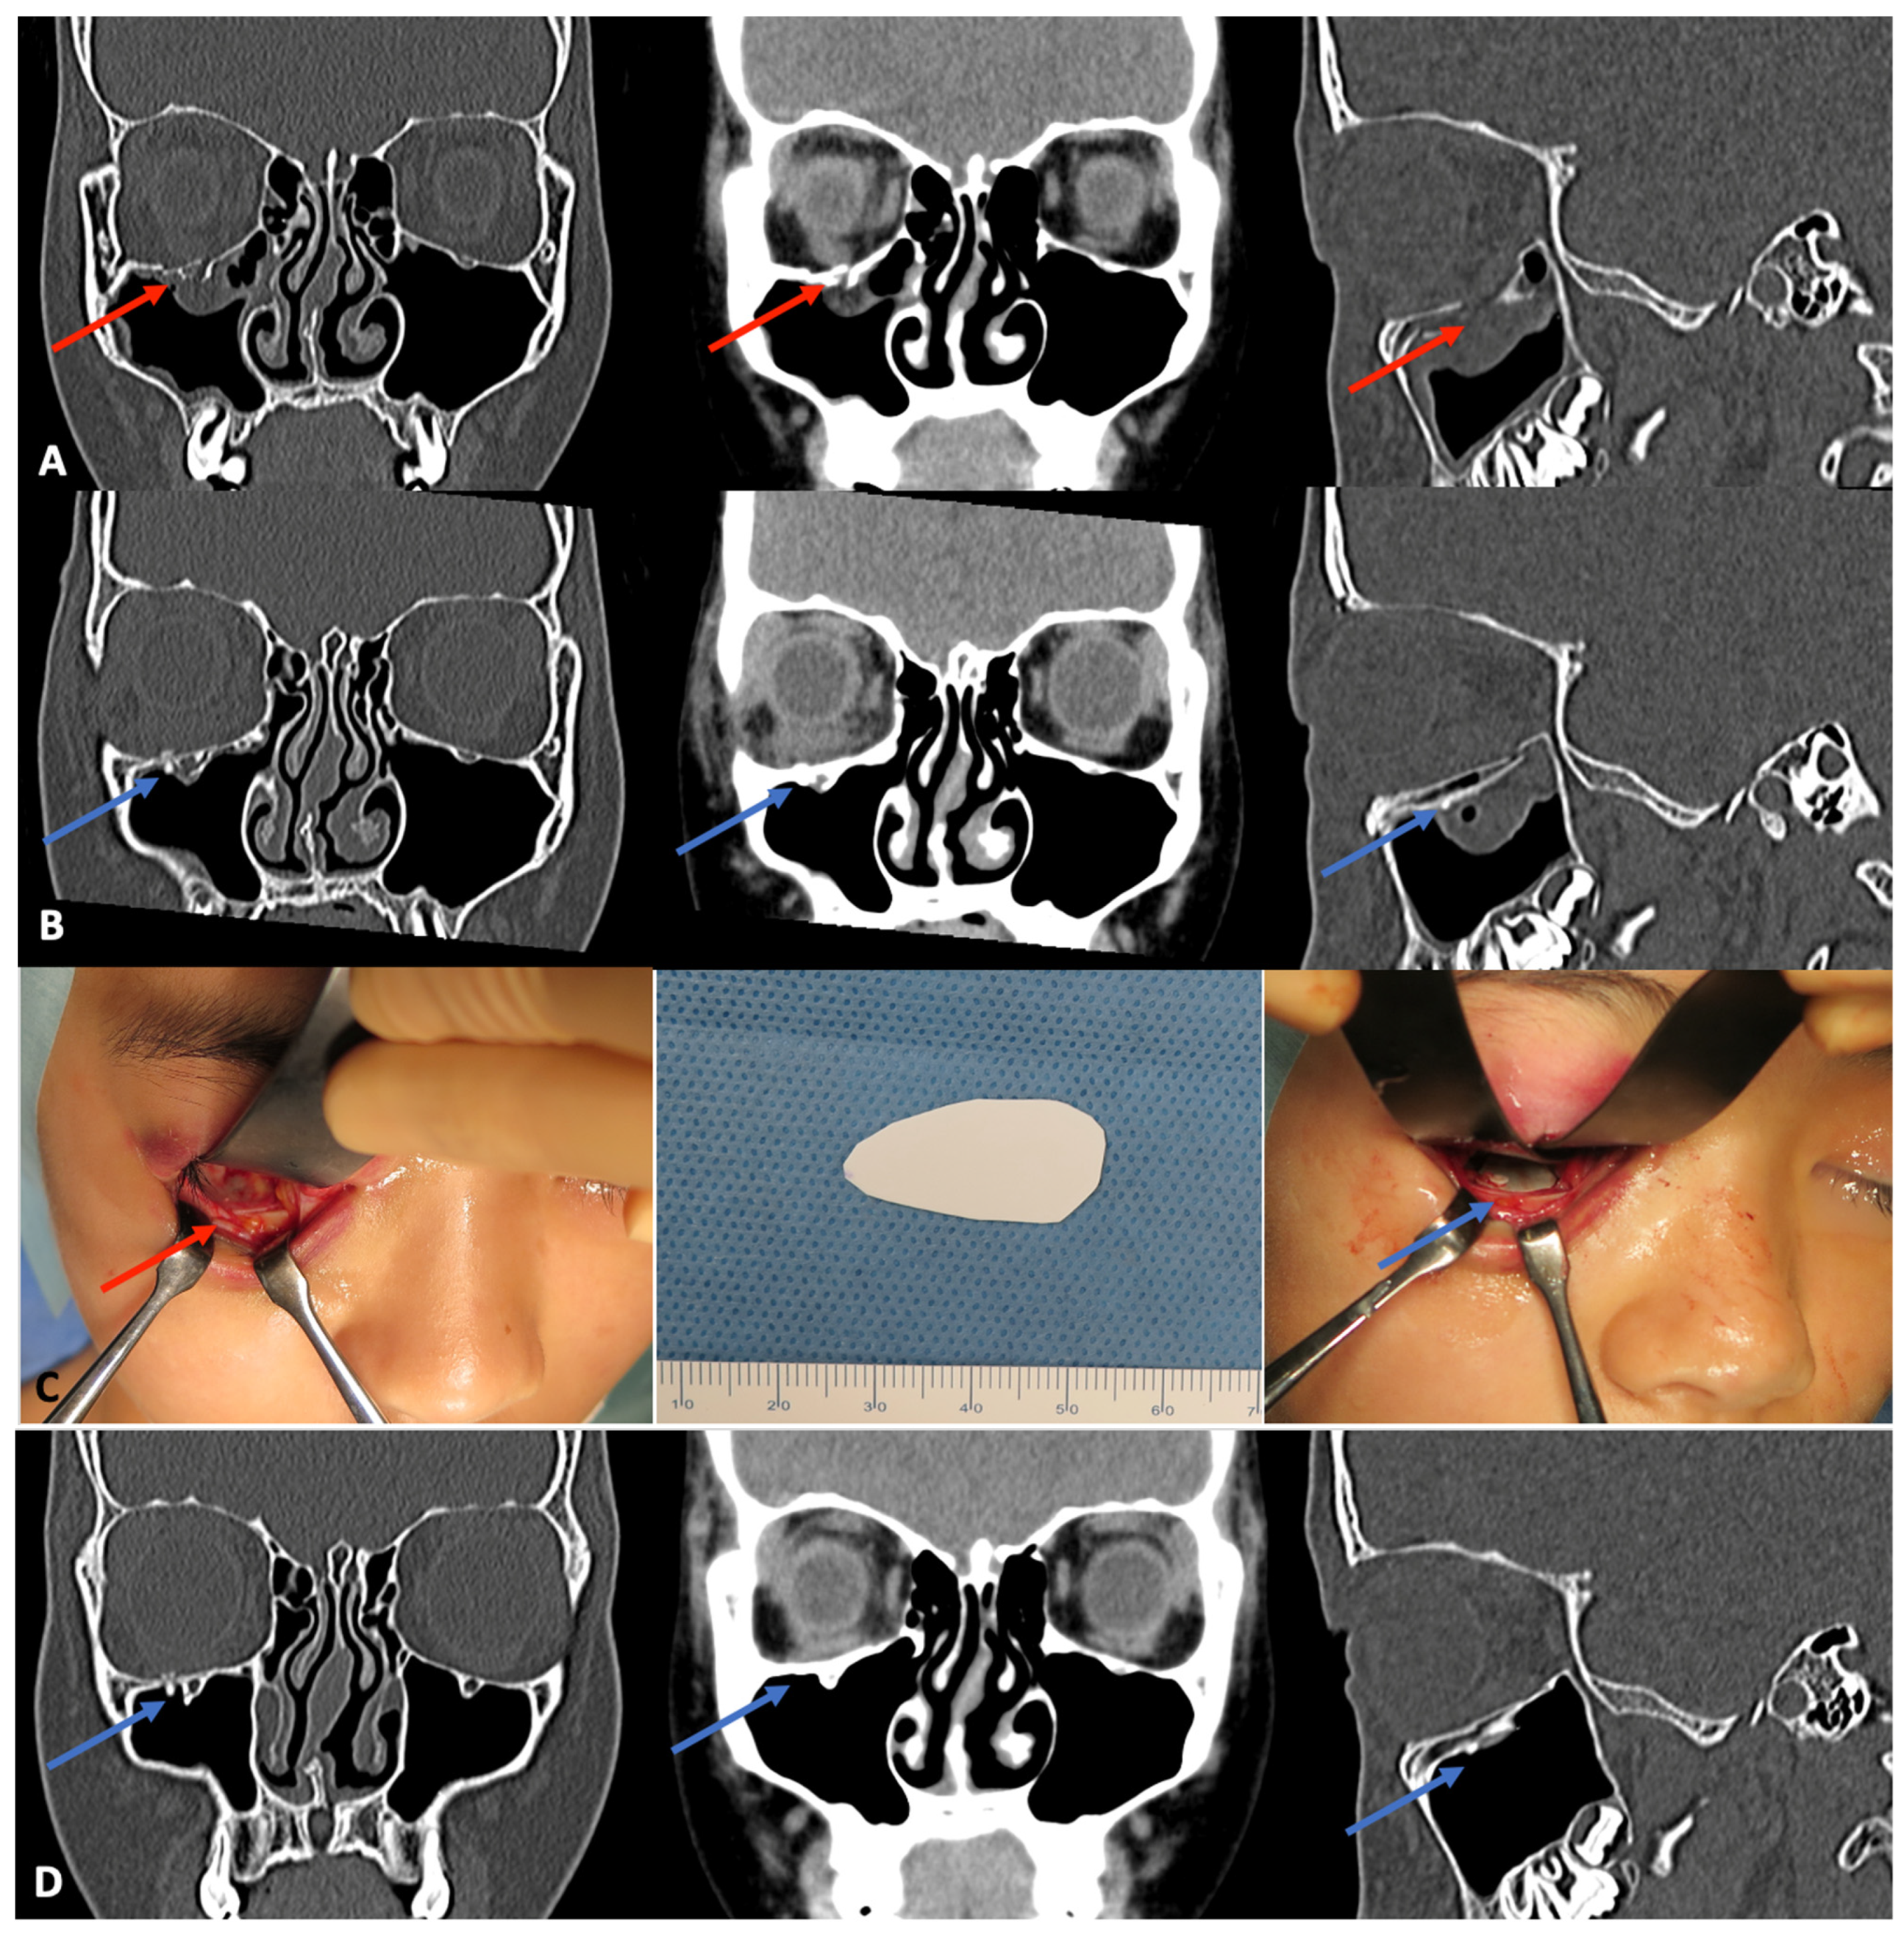

3.1.1. Orbital Wall Fractures

- Tsumiyama, S.; Umeda, G.; Ninomiya, K.; Miyawaki, T. Use of Unsintered Hydroxyapatite and Poly-L-lactic Acid Composite Sheets for Management of Orbital Wall Fracture. J. Craniofac. Surg. 2019, 30, 2001–2003. [Google Scholar] [CrossRef] [PubMed]

- Kohyama, K.; Morishima, Y.; Arisawa, K.; Arisawa, Y.; Kato, H. Immediate and long-term results of unsintered hydroxyapatite and poly L-lactide composite sheets for orbital wall fracture reconstruction. J. Plast. Reconstr. Aesthet. Surg. 2018, 71, 1069–1075. [Google Scholar] [CrossRef] [PubMed]

- Watanabe, A.; Yamanaka, Y.; Rajak, S.N.; Nakayama, T.; Ueda, K.; Sotozono, C. Assessment of a Consecutive Series of Orbital Floor Fracture Repairs With the Hess Area Ratio and the Use of Unsintered Hydroxyapatite Particles/Poly l-Lactide Composite Sheets for Orbital Fracture Reconstruction. J. Oral Maxillofac. Surg. 2021, 79, 420–428. [Google Scholar] [CrossRef]

- Jang, H.U.; Kim, S.Y. Biodegradable implants for orbital wall fracture reconstruction. Arch. Craniofacial Surg. 2020, 21, 99–105. [Google Scholar] [CrossRef]

- Kanno, T.; Karino, M.; Yoshino, A.; Koike, T.; Ide, T.; Tatsumi, H.; Tsunematsu, K.; Yoshimatsu, H.; Sekine, J. Feasibility of Single Folded Unsintered Hydroxyapatite Particles/Poly-L-Lactide Composite Sheet in Combined Orbital Floor and Medial Wall Fracture Reconstruction. J. Hard Tissue Biol. 2017, 26, 237–244. [Google Scholar] [CrossRef]

- Kanno, T.; Tatsumi, H.; Karino, M.; Yoshino, A.; Koike, T.; Ide, T.; Sekine, J. Clinical Report: Applicability of an Unsintered Hydroxyapatite Particles/Poly-L-Lactide Composite Sheet with Tack Fixation for Orbital Fracture Reconstruction. J. Hard Tissue Biol. 2016, 3, 329–334. [Google Scholar] [CrossRef] [Green Version]

- Sukegawa, S.; Kanno, T.; Koyama, Y.; Matsumoto, K.; Sukegawa-Takahashi, Y.; Masui, M.; Tanaka, S.; Furuki, Y. Precision of Post-Traumatic Orbital Reconstruction Using Unsintered Hydroxyapatite Particles/Poly-L-Lactide Composite Bioactive/Resorbable Mesh Plate with and without Navigation: A Retrospective Study. J. Hard Tissue Biol. 2017, 26, 274–280. [Google Scholar] [CrossRef] [Green Version]

- Shintaro, S.; Takahiro, K.; Yuta, K.; Akane, S.; Ken-ichi, M.; Yuka, S.; Kyosuke, S.; Shigeto, T.; Yoshihiko, F. Intraoperative Navigation-assisted Surgical Orbital Floor Reconstruction in Orbital Fracture Treatment: A Case Report. Shimane J. Med. Sci. 2017, 33, 87–92. [Google Scholar]

- Dong, Q.N.; Karino, M.; Koike, T.; Ide, T.; Okuma, S.; Kaneko, I.; Osako, R.; Kanno, T. Navigation-Assisted Isolated Medial Orbital Wall Fracture Reconstruction Using an U-HA/PLLA Sheet via a Transcaruncular Approach. J. Investig. Surg. 2020, 33, 644–652. [Google Scholar] [CrossRef] [PubMed]

- Dong, Q.N.; Ide, T.; Karino, M.; Okuma, S.; Koike, T.; Kanno, T. Retrobulbar Orbital Emphysema Associated with Medial Orbital Wall Fracture. J. Craniofac. Surg. 2019, 30, 1549–1551. [Google Scholar] [CrossRef]

- Hwang, K. In Vivo Degradation of Forged-Unsintered Hydroxyapatite and Poly-L-lactide Mesh Used for Orbital Reconstruction. J. Craniofac. Surg. 2019, 30, 1208–1210. [Google Scholar] [CrossRef] [PubMed]